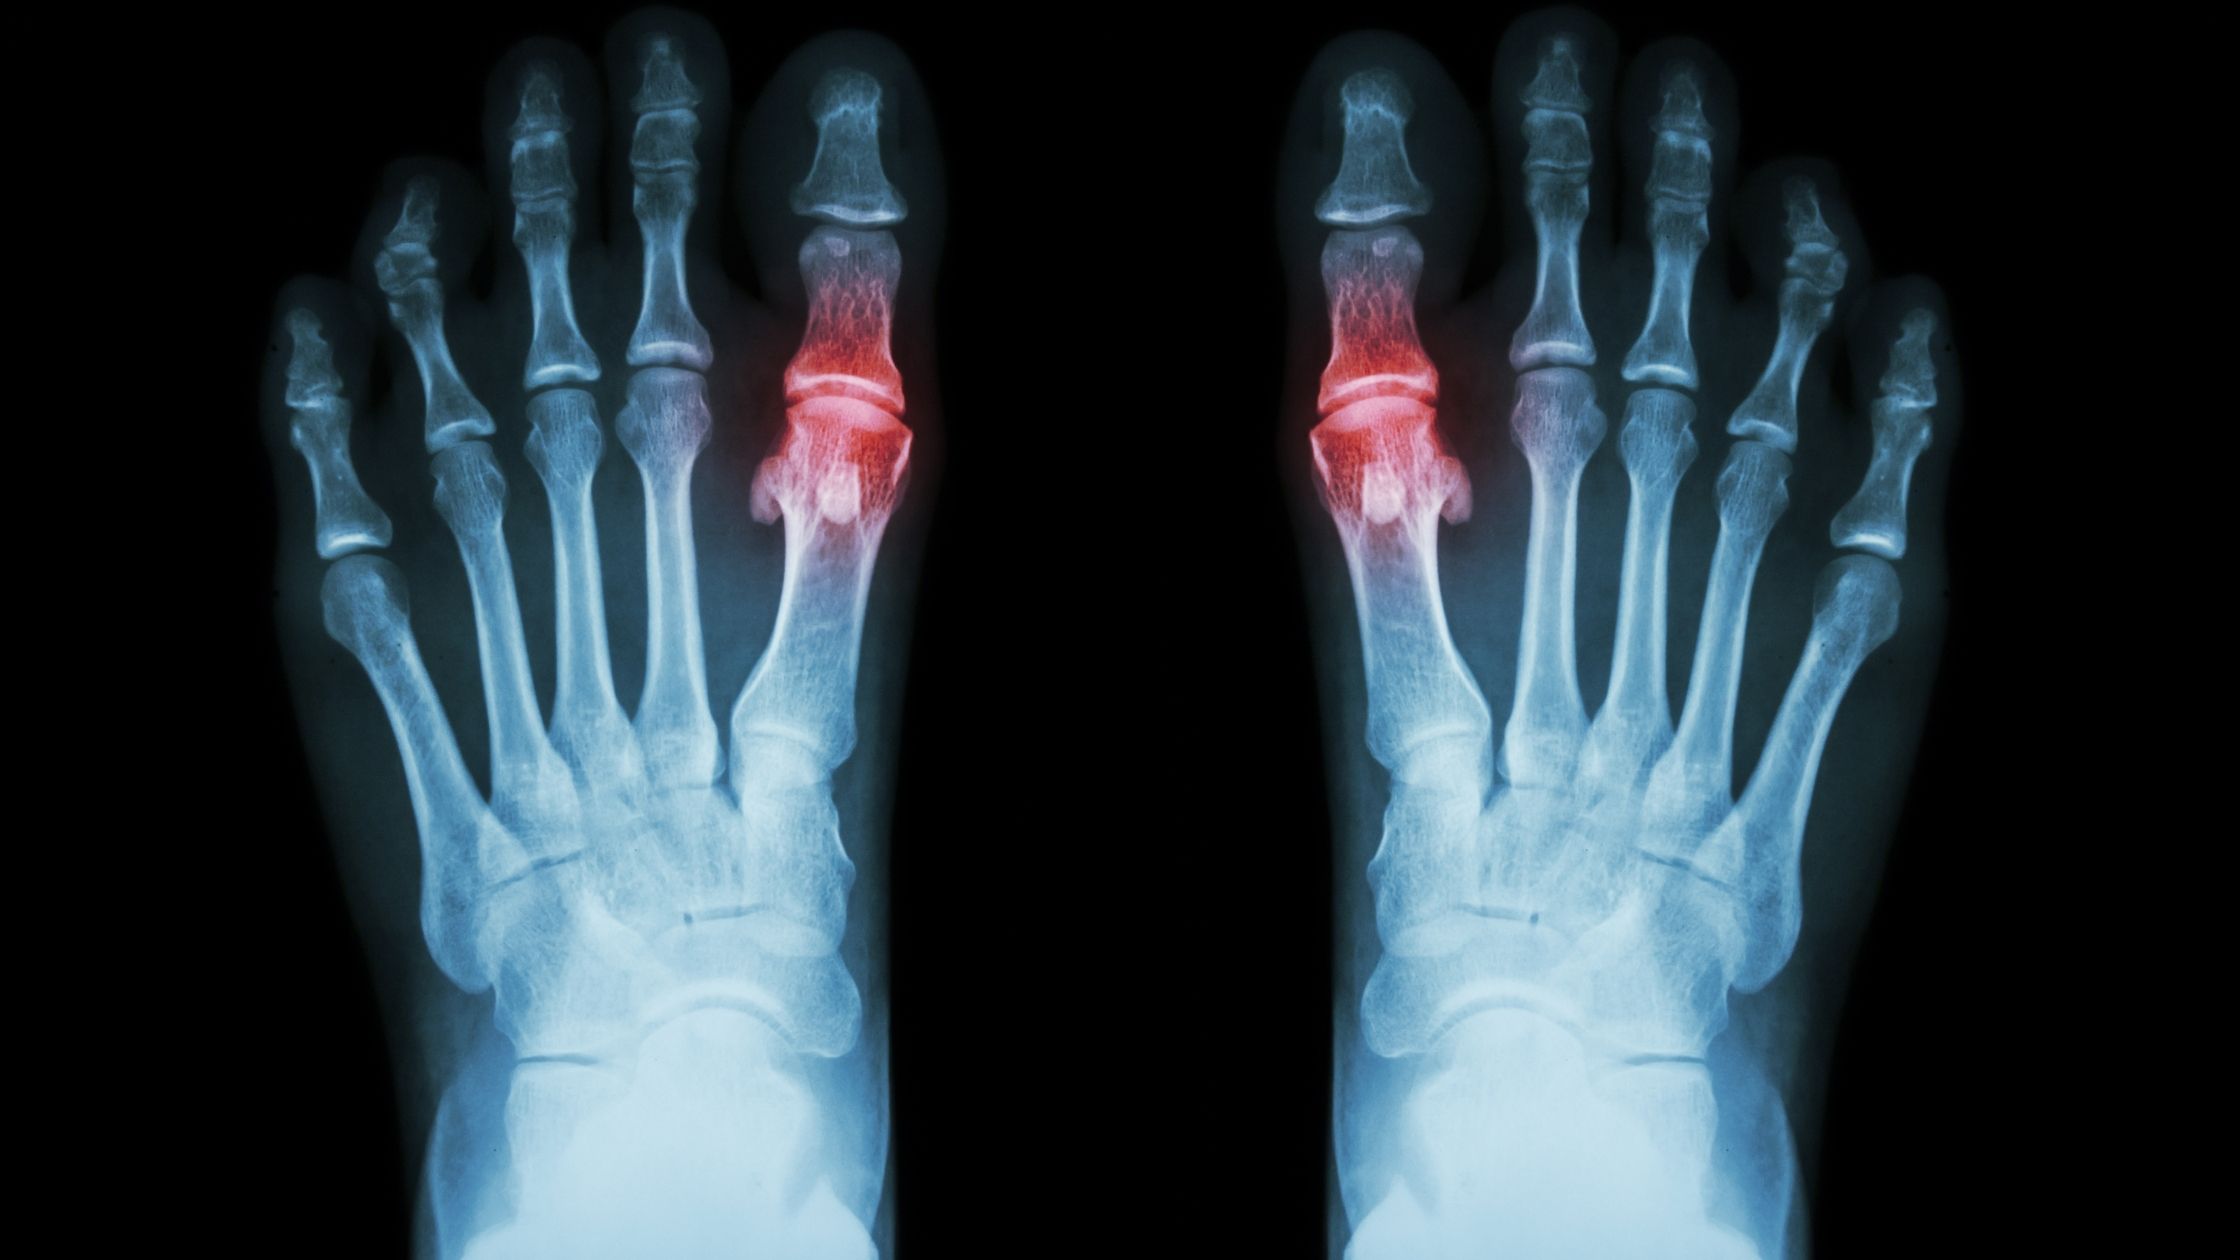

Gout is a very popular joint condition in Malaysia. Around 3-5% of the population is affected by gout.

Gout occurs when there is a buildup of uric acid in the body. Uric acid is only partially soluble in the water. This low solubility causes them to easily crystalise in the blood, especially when water intake is low.

We call these crystals the urate crystals, and they are normally sharp and needle-like.

Gout happens when urate crystals form and accumulate in your joints (normally the smaller joints are more easily affected), causing inflammation and intense pain.

If you have gout, you’ll probably experience painful swelling in your joints, particularly in your feet. You might have intermittent gout attacks, or flare-ups, which involve a sudden onset of pain and swelling.